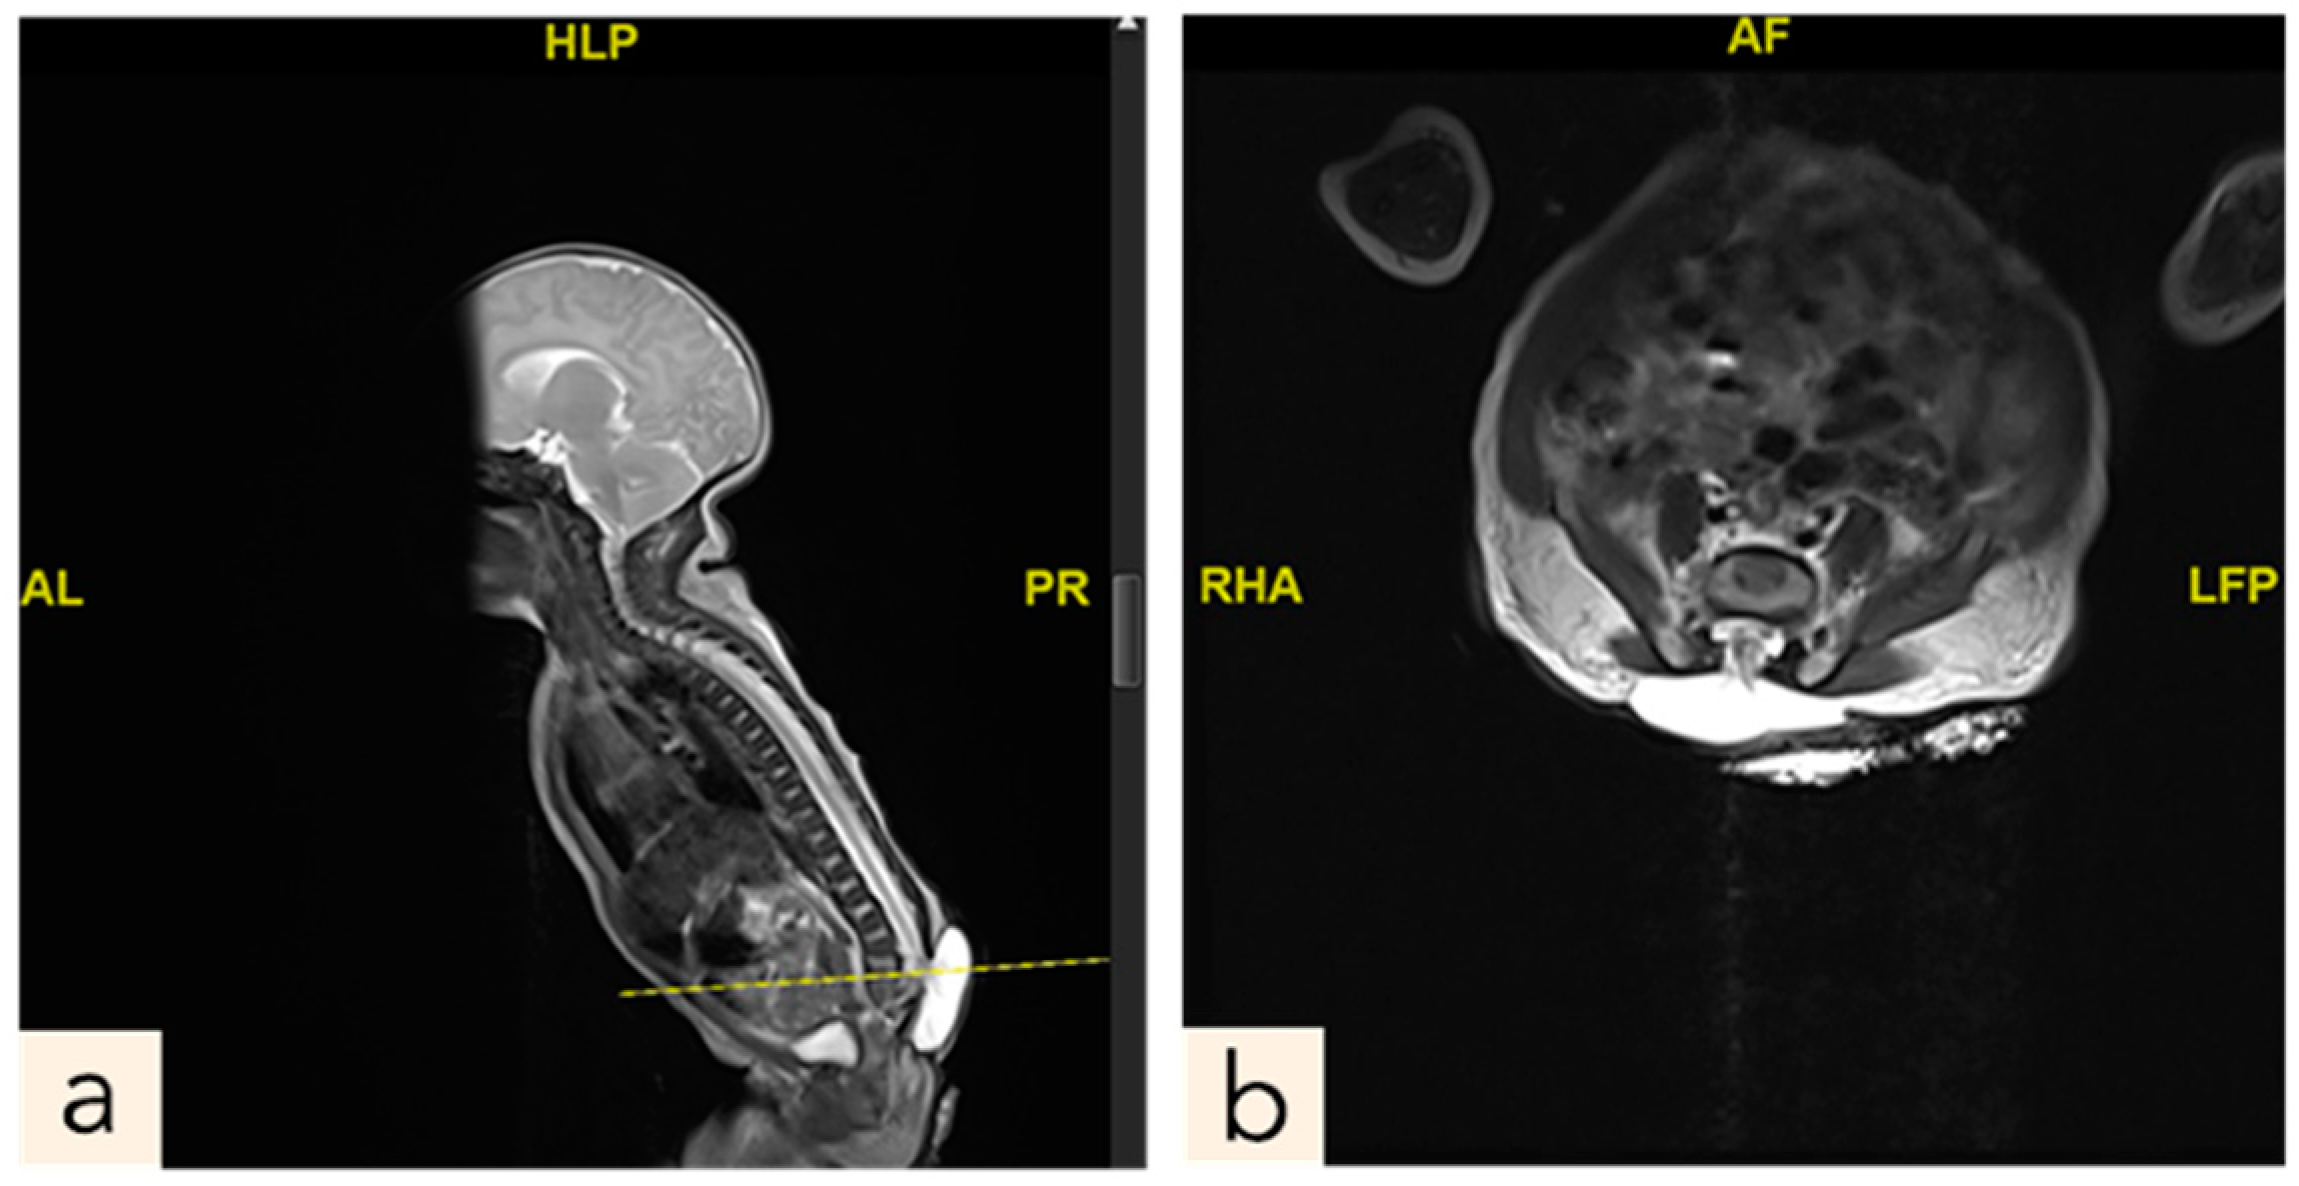

2.1. Patient 1

2.2. Patient 2

2.3. Patient 3

2.4. Patient 4